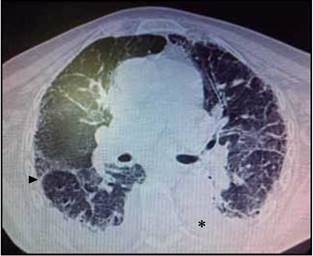

Se toman estudios paraclínicos de extensión que evidencian hemograma con recuento leucocitario normal tendiente al aumento, con predominio neutrofílico (90%), anemia leve con volúmenes conservados y trombocitopenia leve, gases arteriales con acidosis respiratoria (pH 7.31, CO2 45, PO2 55), función renal y electrolitos en rangos de normalidad. Estudios imagenológicos donde se toma doppler dúplex venoso de miembros inferiores sin alteraciones y tomogra-fía axial computarizada (TAC) de tórax la cual documenta neumopatía intersticial en patrón de panal de abejas, con derrame pleural bilateral y atelectasias (Figura 3).